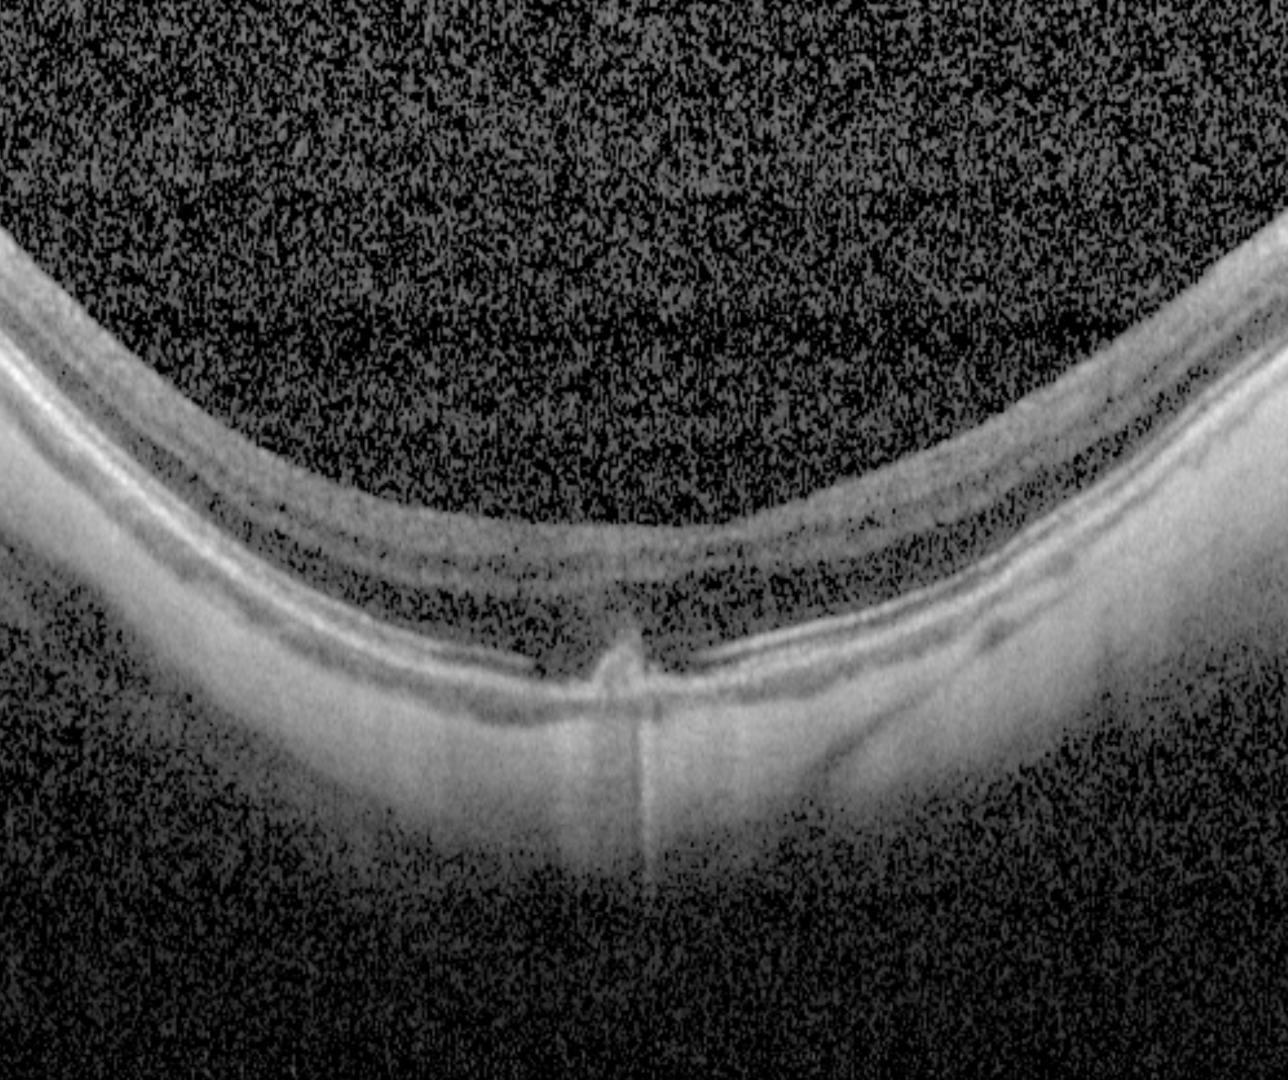

Spectralis OCT line scan (right macula)

When associated with a lacquer crack, OCT shows a hypo-reflective break in the RPE-Bruch's membrane complex with a "volcanic"-like appearance. There are no signs of associated exudation present.

When associated with myopic CNV, the CNV presents on OCT as a hyper-reflective sub-retinal lesion usually with associated subretinal fluid. More information about myopic CNV is available by clicking on the tab at the bottom of this page.

A 59 year old Caucasian female with refraction -8.75/-0.5 x 22 and best corrected visual acuity of 6/15 (20/50) in the right eye.